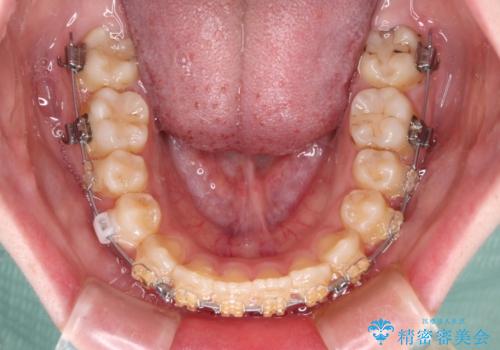

- 矯正装置

- 審美装置

舌の突出癖があり、それが原因で上下前歯に隙間ができていたため、改善のためのトレーニングを行うように指示をしました。

舌の突出癖の影響か、なかなかスペースが閉じきらず、治療期間は予定よりも長期間となりました。

舌突出癖改善のトレーニングの重要性を認識することとなりました。